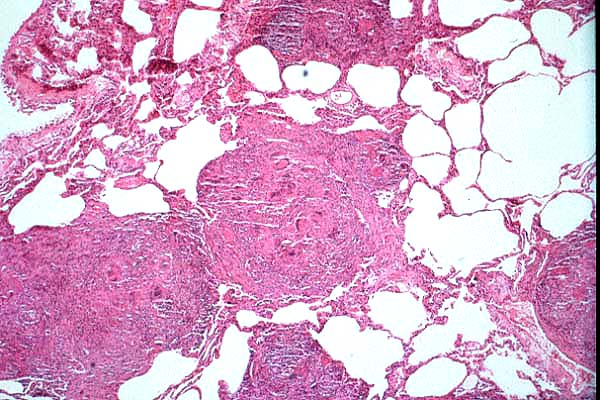

- Case 23-1. Multifocally within the lung, there are

fibrotic foci (e,f) that contain neutrophils (f,g), epithelioid

cells (f,g), occasional foreign body giant cells (e,f,g), and

scattered 8-12u diameter yeast bodies (f,g).